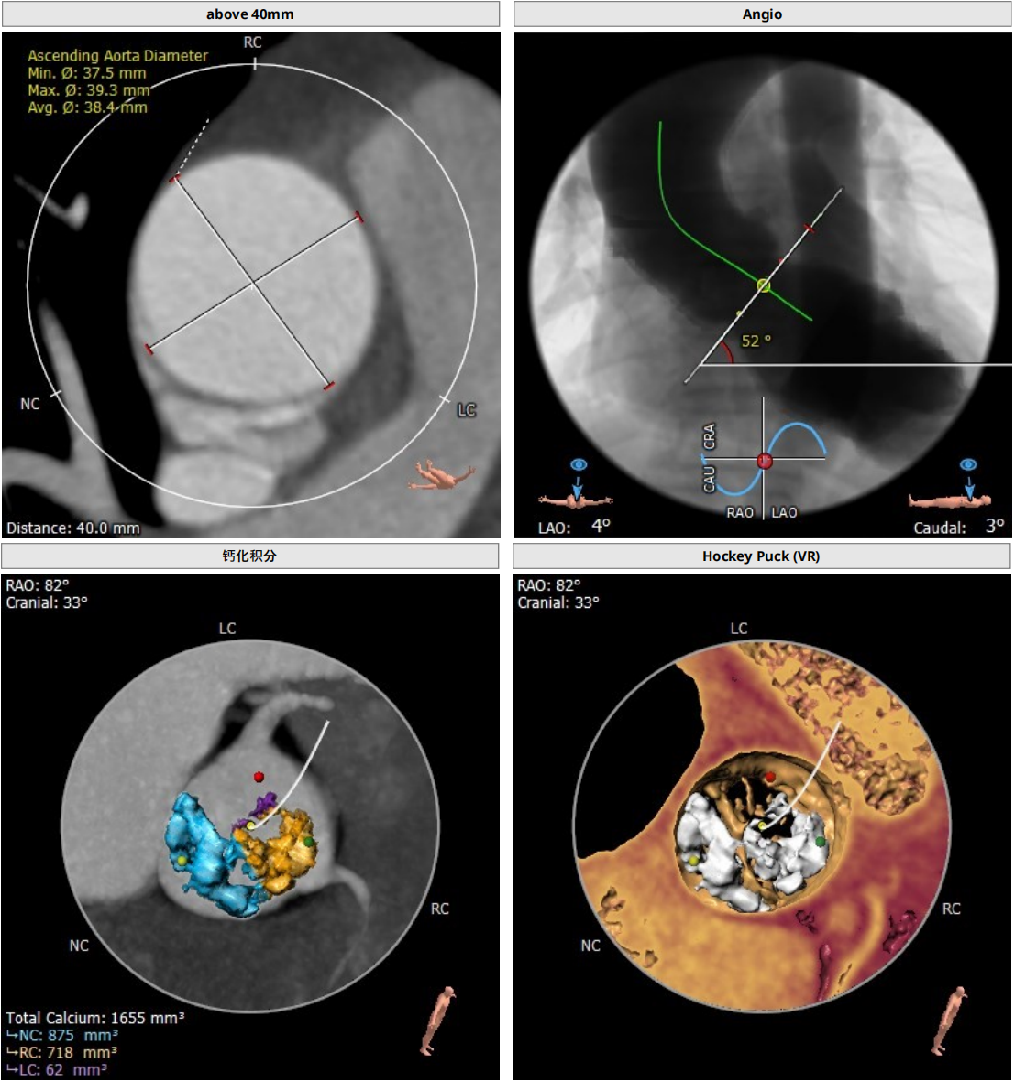

type1型二叶瓣,重度钙化

钙化主要分布在右冠窦和无冠窦

左冠高度稍低,存在一定冠脉风险

Annulus:25.8mm

LVOT:27.1mm

STJ 30.6mm

升主动脉:38.4mm

LM:10mm

RM:12.2mm

以3个窦消失最低点确认的平面作为虚拟瓣环平面初步筛选瓣膜尺寸。自展瓣参考周长得出的Annulus直径,该病人为25.8,根据自膨胀瓣膜特点需要oversize,初步判断为29/32瓣膜。LVOT直径大于Annulus,短径24mm,足够限制瓣膜,提供锚定支撑力。STJ高度足够,可提供足够空间给原有瓣叶,过宽的STJ则无法提供释放中锚定支撑力。

窦部的空间与左右冠脉开口高度结合瓣叶形态,是否增厚可以初步判断瓣叶是否会在瓣膜植入后遮挡冠脉开口造成急性的冠脉堵塞。该病人左冠开口略低,且钙化集中在右冠和无冠窦,判断冠脉风险较高。需术中球扩判断是否进行冠脉保护。

升主动脉未见增宽,心脏角度合适极重度钙化,多集中在基底部位二叶瓣重度钙化THV需要downsize选择26/29瓣膜。

钙化积分:

0-400 轻度

400-600 中度

600-800 重度

800以上 极重度钙化